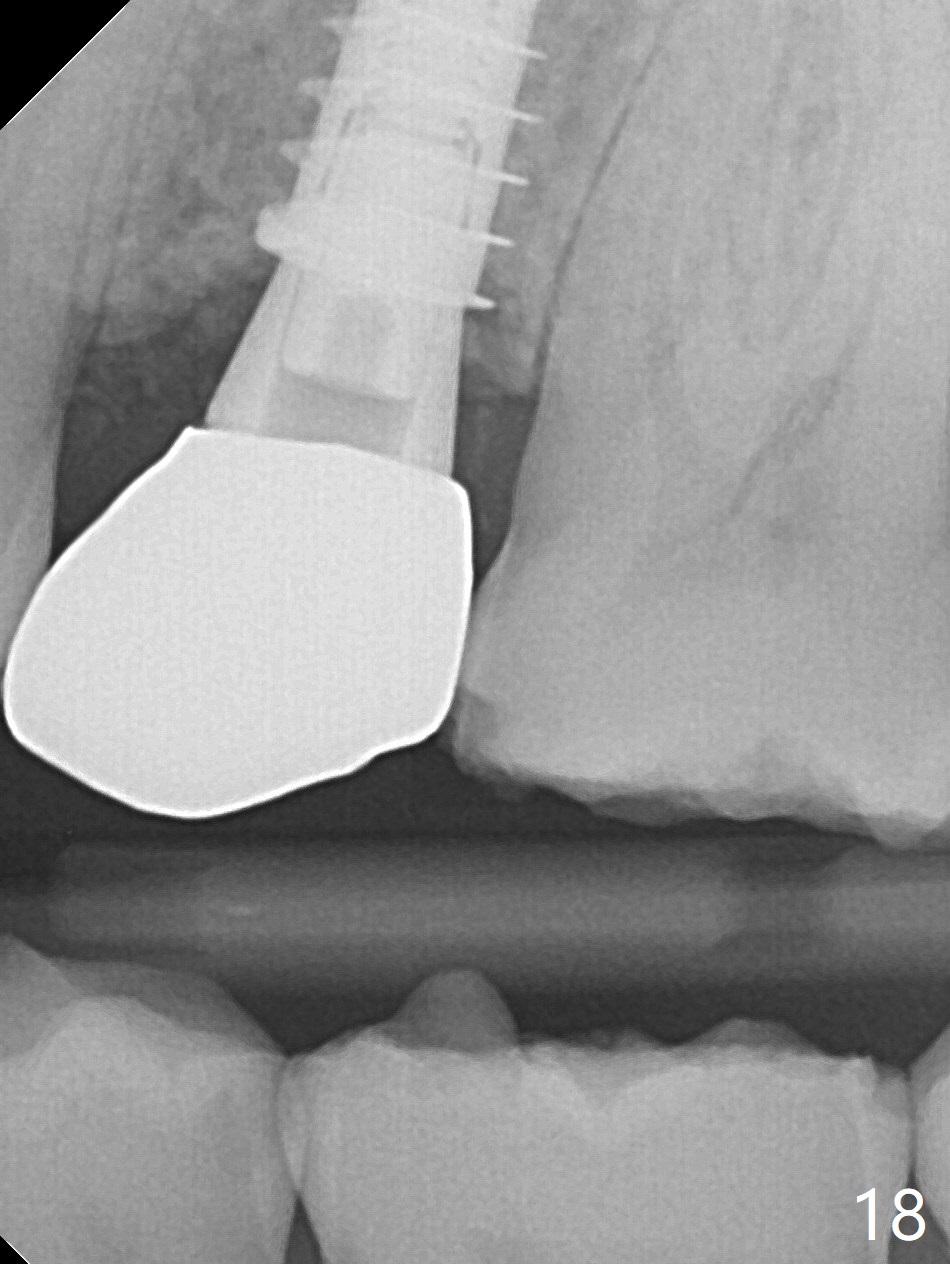

The buccal gingival inflammation subsides 1 week postop (Fig.13,14). There is no bone loss 4 months postop (Fig.15,16). The crown is recemented 6 months post cementation (probably due to short abutment); there is a residual cement (Fig.17 <), which is removed (Fig.18).